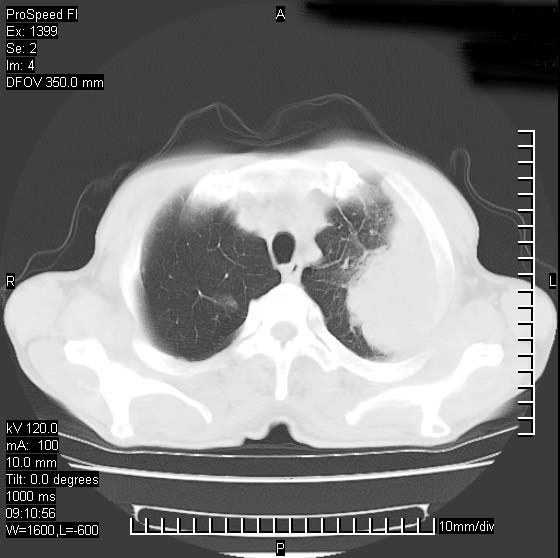

以下是引用rgsyyf在2007-1-19 11:05:00的发言:[br]左肺上叶见形态不规则巨大软组织肿块影,边缘呈分叶征,纵隔内隆突下见肿大淋巴结,右肺内另见一不规则结节影 .考虑:左肺周围性肺癌伴纵隔即右肺内转移.